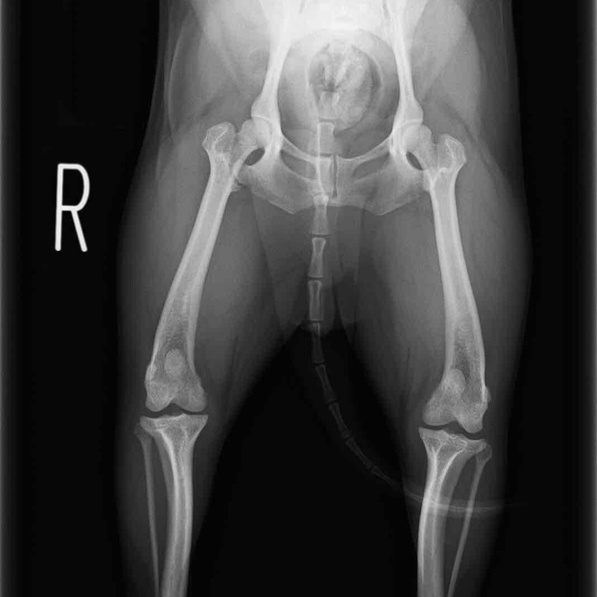

左後肢の挙上を主訴に来院されました。触診にて両関節の前方引き出し兆候、両膝蓋骨の内方脱臼を認めました。関節液検査より免疫介在性多発性関節炎は否定的でした。レントゲン検査にてfat pad signを伴う関節炎が認められたことから、前十字靭帯断裂と膝蓋骨内方脱臼(左GradeⅢ 右GradeⅢ〜IV)併発と診断し、手術を行いました。

手術は片足ずつ行い、両膝とも術中の関節鏡検査にて前十字靭帯の完全断裂と半月板損傷を確認しました。TPLO、半月板切除と滑車溝形成を始めとした膝蓋骨脱臼整復術を実施いたしました。膝蓋骨の安定化を測るために外側支帯を強固に縫合し、内側支帯は切除し縫合せずに開放状態にしています。

術前正面像

術前のTPAは左後肢33.1°右後肢26.8°でしたがTPLO実施により左後肢5.5°右後肢12°に矯正されました。